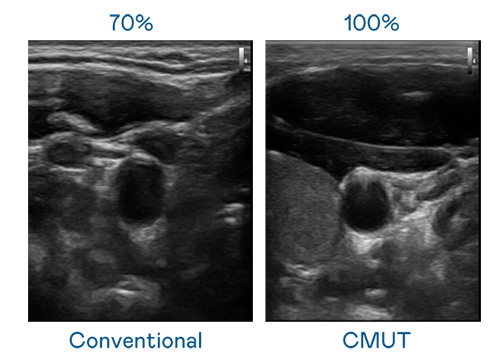

CMUT 技术是一种用电容式微机电元件来产生超音波讯号的技术。与传统 PZT 压电式技术相比,CMUT 频宽增加 30%,更宽频的超音波讯号让影像解析度大幅提升,是实现高影像品质医疗超音波扫描、促进精准医疗发展的关键技术。

大频宽带来超清晰影像

超音波影像的解析度高低,首先取决于探头能发出的讯号频宽。人生就是搏 CMUT 可提供高清晰的超音波讯号,提供高频宽、高灵敏度、影像纹理细节更高的超音波影像,协助医护人员缩短影像判读时间及利用精准的医疗影像进行诊断。